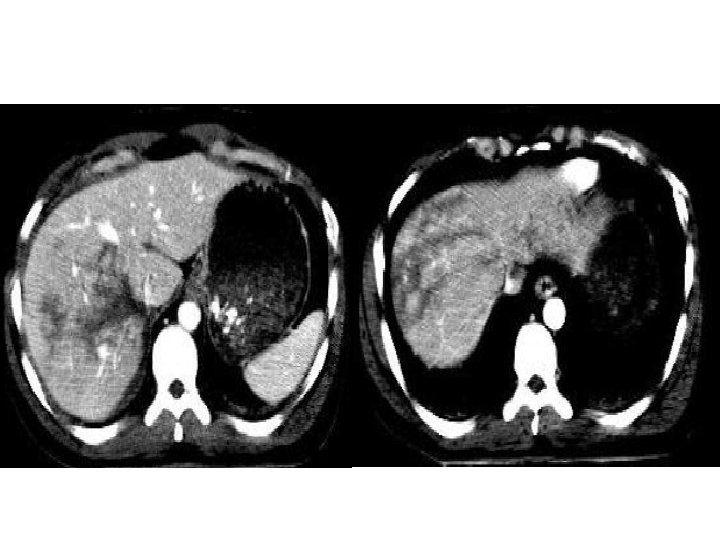

Trauma hepático Melhor exame: TC - S = 100% - E = 94% • Pista diagnóstica: evidência de lesão parenquimatosa irregular associada a hemorragia intra e perihepática • Lobo direito: 75% • 2ª víscera mais afetada no trauma * Maioria dos hematomas subcapsulares são iatrogênicos pós-biópsias • Suspeitar: dor, sensibilidade, rebote +, defesa, hipotensão, hematêmese/melena (hemobilia), icterícia. Lab: de Br e FA

Trauma hepático – achados na TC • Lacerações: – Simples: lesão hipodensa linear solitária; – “Estrelada”: lesões hipodensas lineares ramificadas (paralela aos ramos da veia porta ou hepática) – Superficial: < 3 cm; profunda: > 3 cm • Hematoma: parenquimatoso x sucapsular (formato lenticular) – Não coagulado (menos tempo): hiperdenso em relação ao parênquima hepático não contrastado e hipodenso em relação ao contrastado – Coagulado: mais denso que o não coagulado

Hemorragia ativa: área focal de atenuação de contraste em fase arterial. Se persistir: falha no tratamento conservador